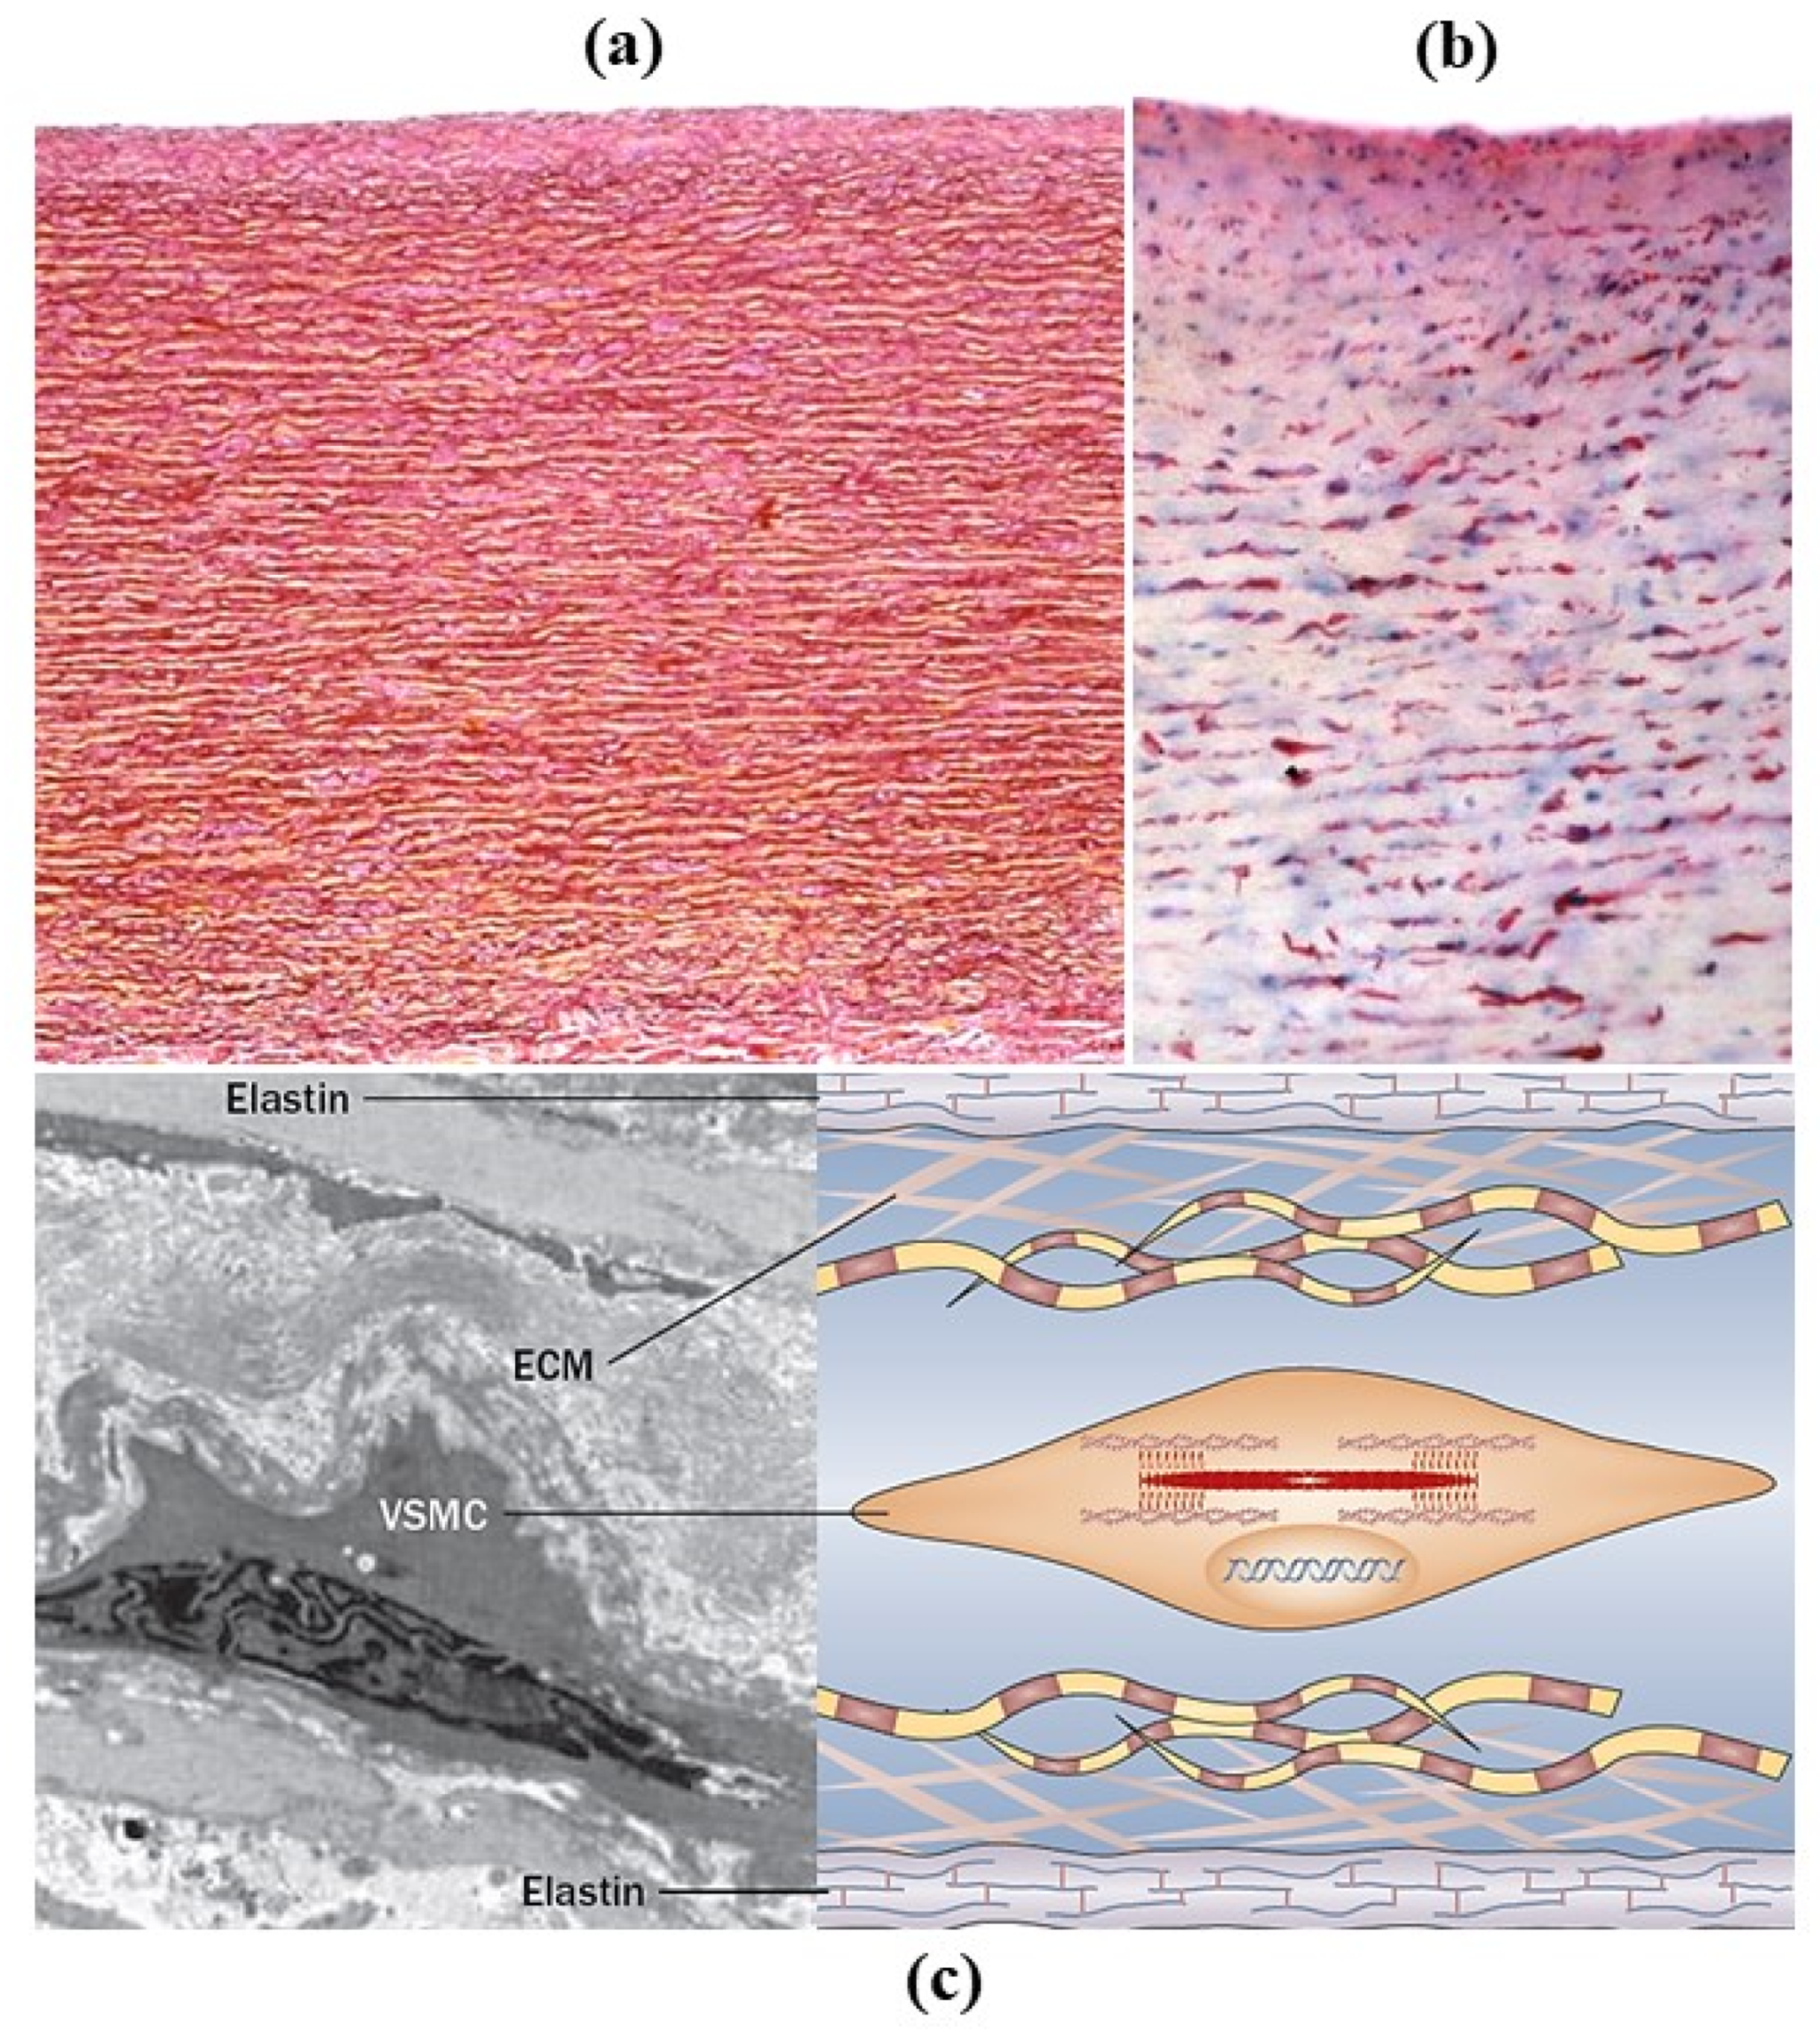

2. Normal Anatomy